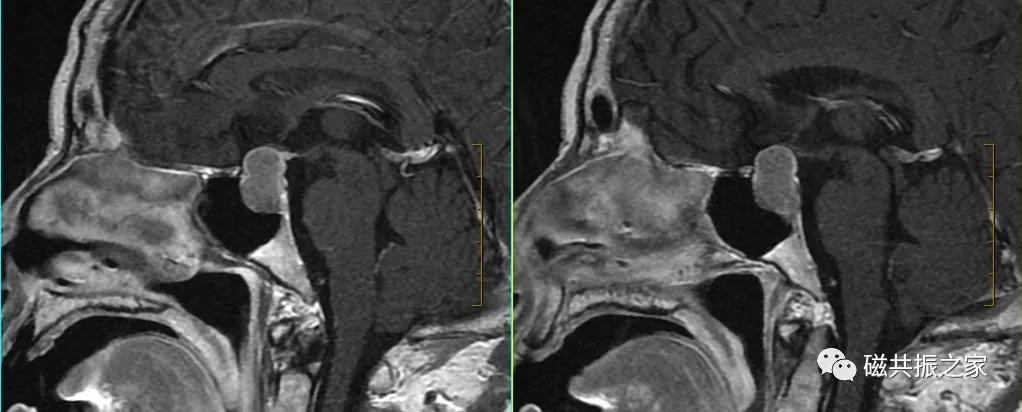

冠状位:COR Dynamic T1 FSE 冠状位T1多期动态增强序列

以矢状位和横断位作为参考定位。定位方法同上面的平扫序列,双侧对称扫描,扫描范围包括整个垂体,为了保证时间分辨率,扫描层数不宜过多,5-7层。注射对比剂前先扫描一期蒙片,暂停,然后注射对比剂的同时开始连续的动态扫描(1.5T:8-10期,每一期20S左右最佳,3.0T:15-20期,每期10S左右最佳),整个动态增强序列扫描3min左右即可。

动态增强通常采用冠状面扫描。注射对比剂前扫描一期蒙片的目的:评估扫描所得的图像质量是否能满足诊断要求,包括范围、信噪比,伪影等。

为了保证足够的信噪比应适当的加大FOV,减小矩阵。

动态增强扫描建议使用脂肪抑制;如时间不允许也可不使用脂肪抑制,但在后面的延迟扫描中需使用脂肪抑制。

不使用饱和带,可缩短扫描时间。

为了保证时间分辨率扫描层数不宜过多,回波链可适当加长(可以加到5)。

造影剂采用半剂量:0.1ml/kg或者0.05mmol/kg,速率2-3ml/s。

注射对比剂的同时开始连续的动态增强扫描;也有采用注射对比剂后延迟5s后,再开始扫描的,这两种扫描方式均可。

扫描后的图像做动态增强曲线后处理分析。

根据垂体的血供关系,垂体增强化顺序为垂体漏斗部及后叶、垂体柄、垂体前叶。

垂体无血-脑屏障,在注射造影剂后的早期即可发生强化,而大多数的微腺瘤由垂体的门脉系统供血,其强化比正常垂体慢,在注射造影剂后早期表现为弱强化或不强化,延迟期较正常垂体强化或不强化;但也存在少数的微腺瘤由颈内动脉直接供血,在增强早期也会发生强化。

据部分文献报道在注入对比剂早期即30-90S和1-3min为垂体微腺瘤的最佳对比时间。

COR Dynamic T1 FSE扫描完成后,分别行延迟期的SAG T1+C及COR T1+C序列扫描。

由于动态增强采用压脂技术,延迟扫描的序列可以不使用压脂。